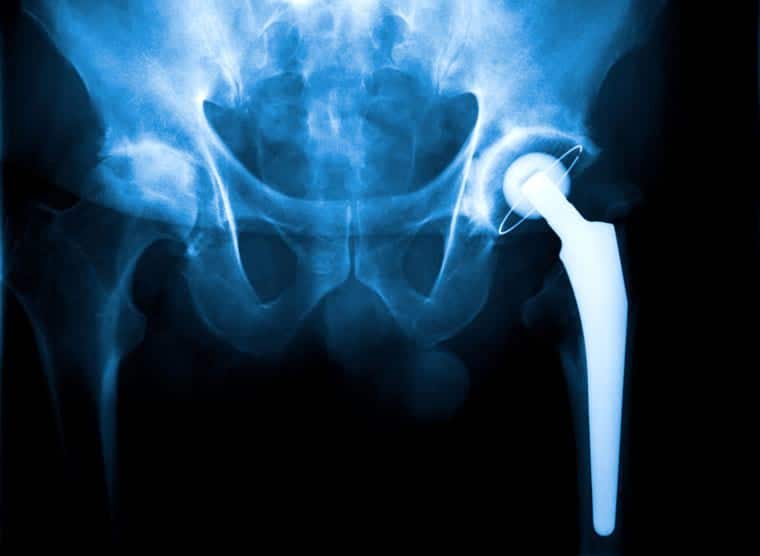

רשלנות רפואית במסגרת ניתוח מפרק ירך

ניקול (שם בדוי), תושבת צרפת, הגיעה לפני מספר שנים לביקור בישראל. תל אביב, העיר הגדולה, קסמה לה מאד וכך גם אתרים אחרים במדינה. את ביקורה בילתה לא מעט על חוף הים, לצד בני משפחתה, ונהנתה מחופשה מהנה במיוחד. לצערה של ניקול, במהלך שהותה בארץ פרקה את הירך. היא נותחה ברגל ימין, ניתוח מפרק ירך, ניתוח שנועד להחליף את המפרק במפרק מלאכותי.

במהלך ניתוח זה נפגע העצב ברגלה, פגיעה שגרמה לה לנכות, הבאה לידי ביטוי בצניחת כף רגל. מדובר בנזק בלתי הפיך, שבעקבותיו החליטה ניקול לתבוע תביעת רשלנות רפואית את המרכז הרפואי שבו בוצע הניתוח.

לאחר התייעצות עם עורך דינה, החליטה ניקול שלא לוותר ופנתה אל בית המשפט בשנית וערערה על פסק הדין שנקבע. בטענותיה בערעור זה טענה ניקול כי הנזק שנגרם לה, נגרם כתוצאה מהתותב שהושתל ברגלה, כבר בעת ההשתלה עצמה, אז נבדק השתל ונפרק תוך כדי הבדיקה. בטענותיה היא מוסיפה כי גם הלחץ שהופעל על השתל במהלך הניתוח הוסיף לא מעט לנזק ואף החמיר אותו.